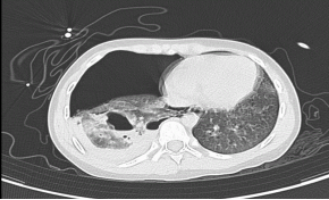

02 创伤性血气胸的急诊处理

胸腔闭式引流:快速解除气胸、血胸对肺的压迫。

胸腔镜微创手术(VATS):用于持续出血或复杂血气胸的探查与止血,肋骨内固定,创伤小、恢复快。